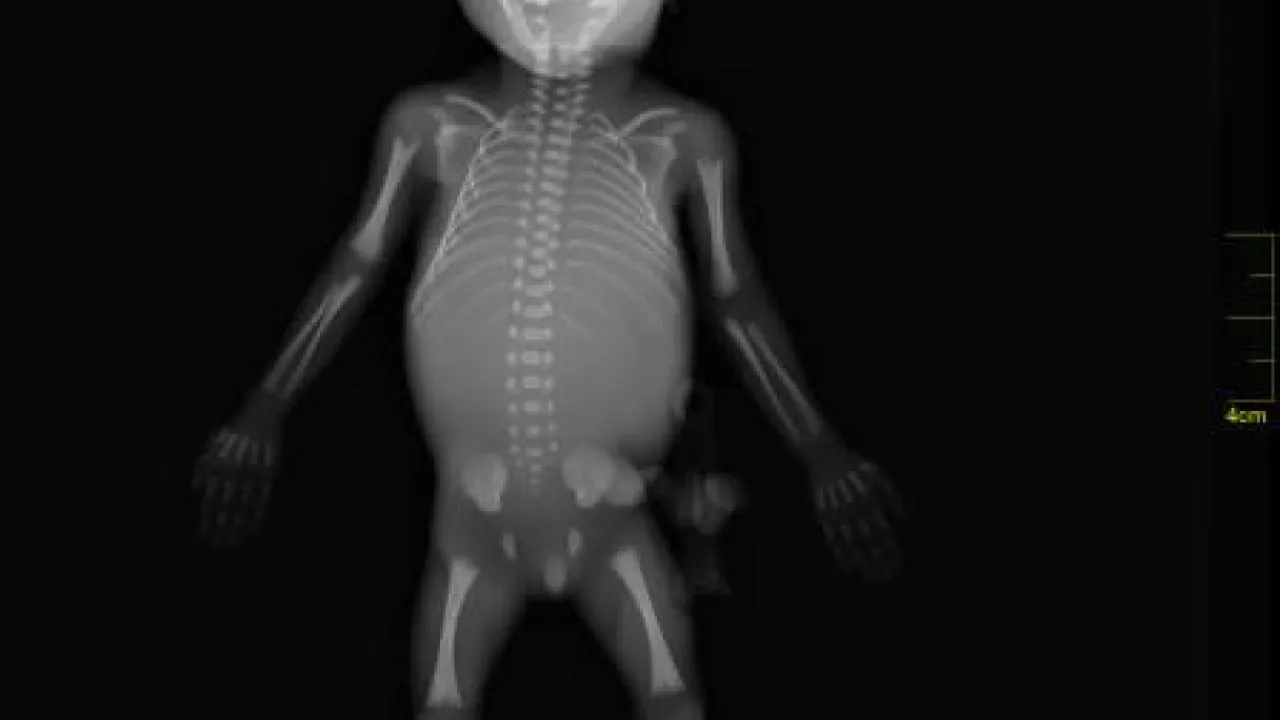

Skeleton, Twin reversed arterial profusion sequence